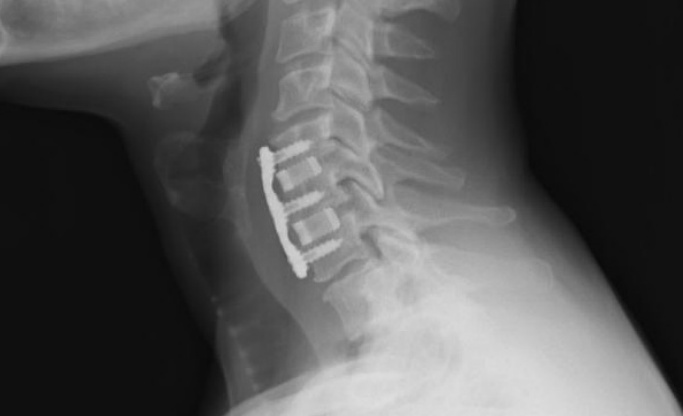

頸椎、脊柱

由氮化硅復(fù)合材料制作的頸椎間隔器和脊柱融合器已投入使用,并取得了成功的臨床結(jié)果。尤其在脊柱方面,多孔氮化硅制備的脊柱椎間體融合手術(shù)的植入材料,在澳大利亞的臨床應(yīng)用已經(jīng)超過15年;致密氮化硅在美國的脊柱應(yīng)用中植入超過3年。

氮化硅頸椎植入物(圖片來源:Sintx)